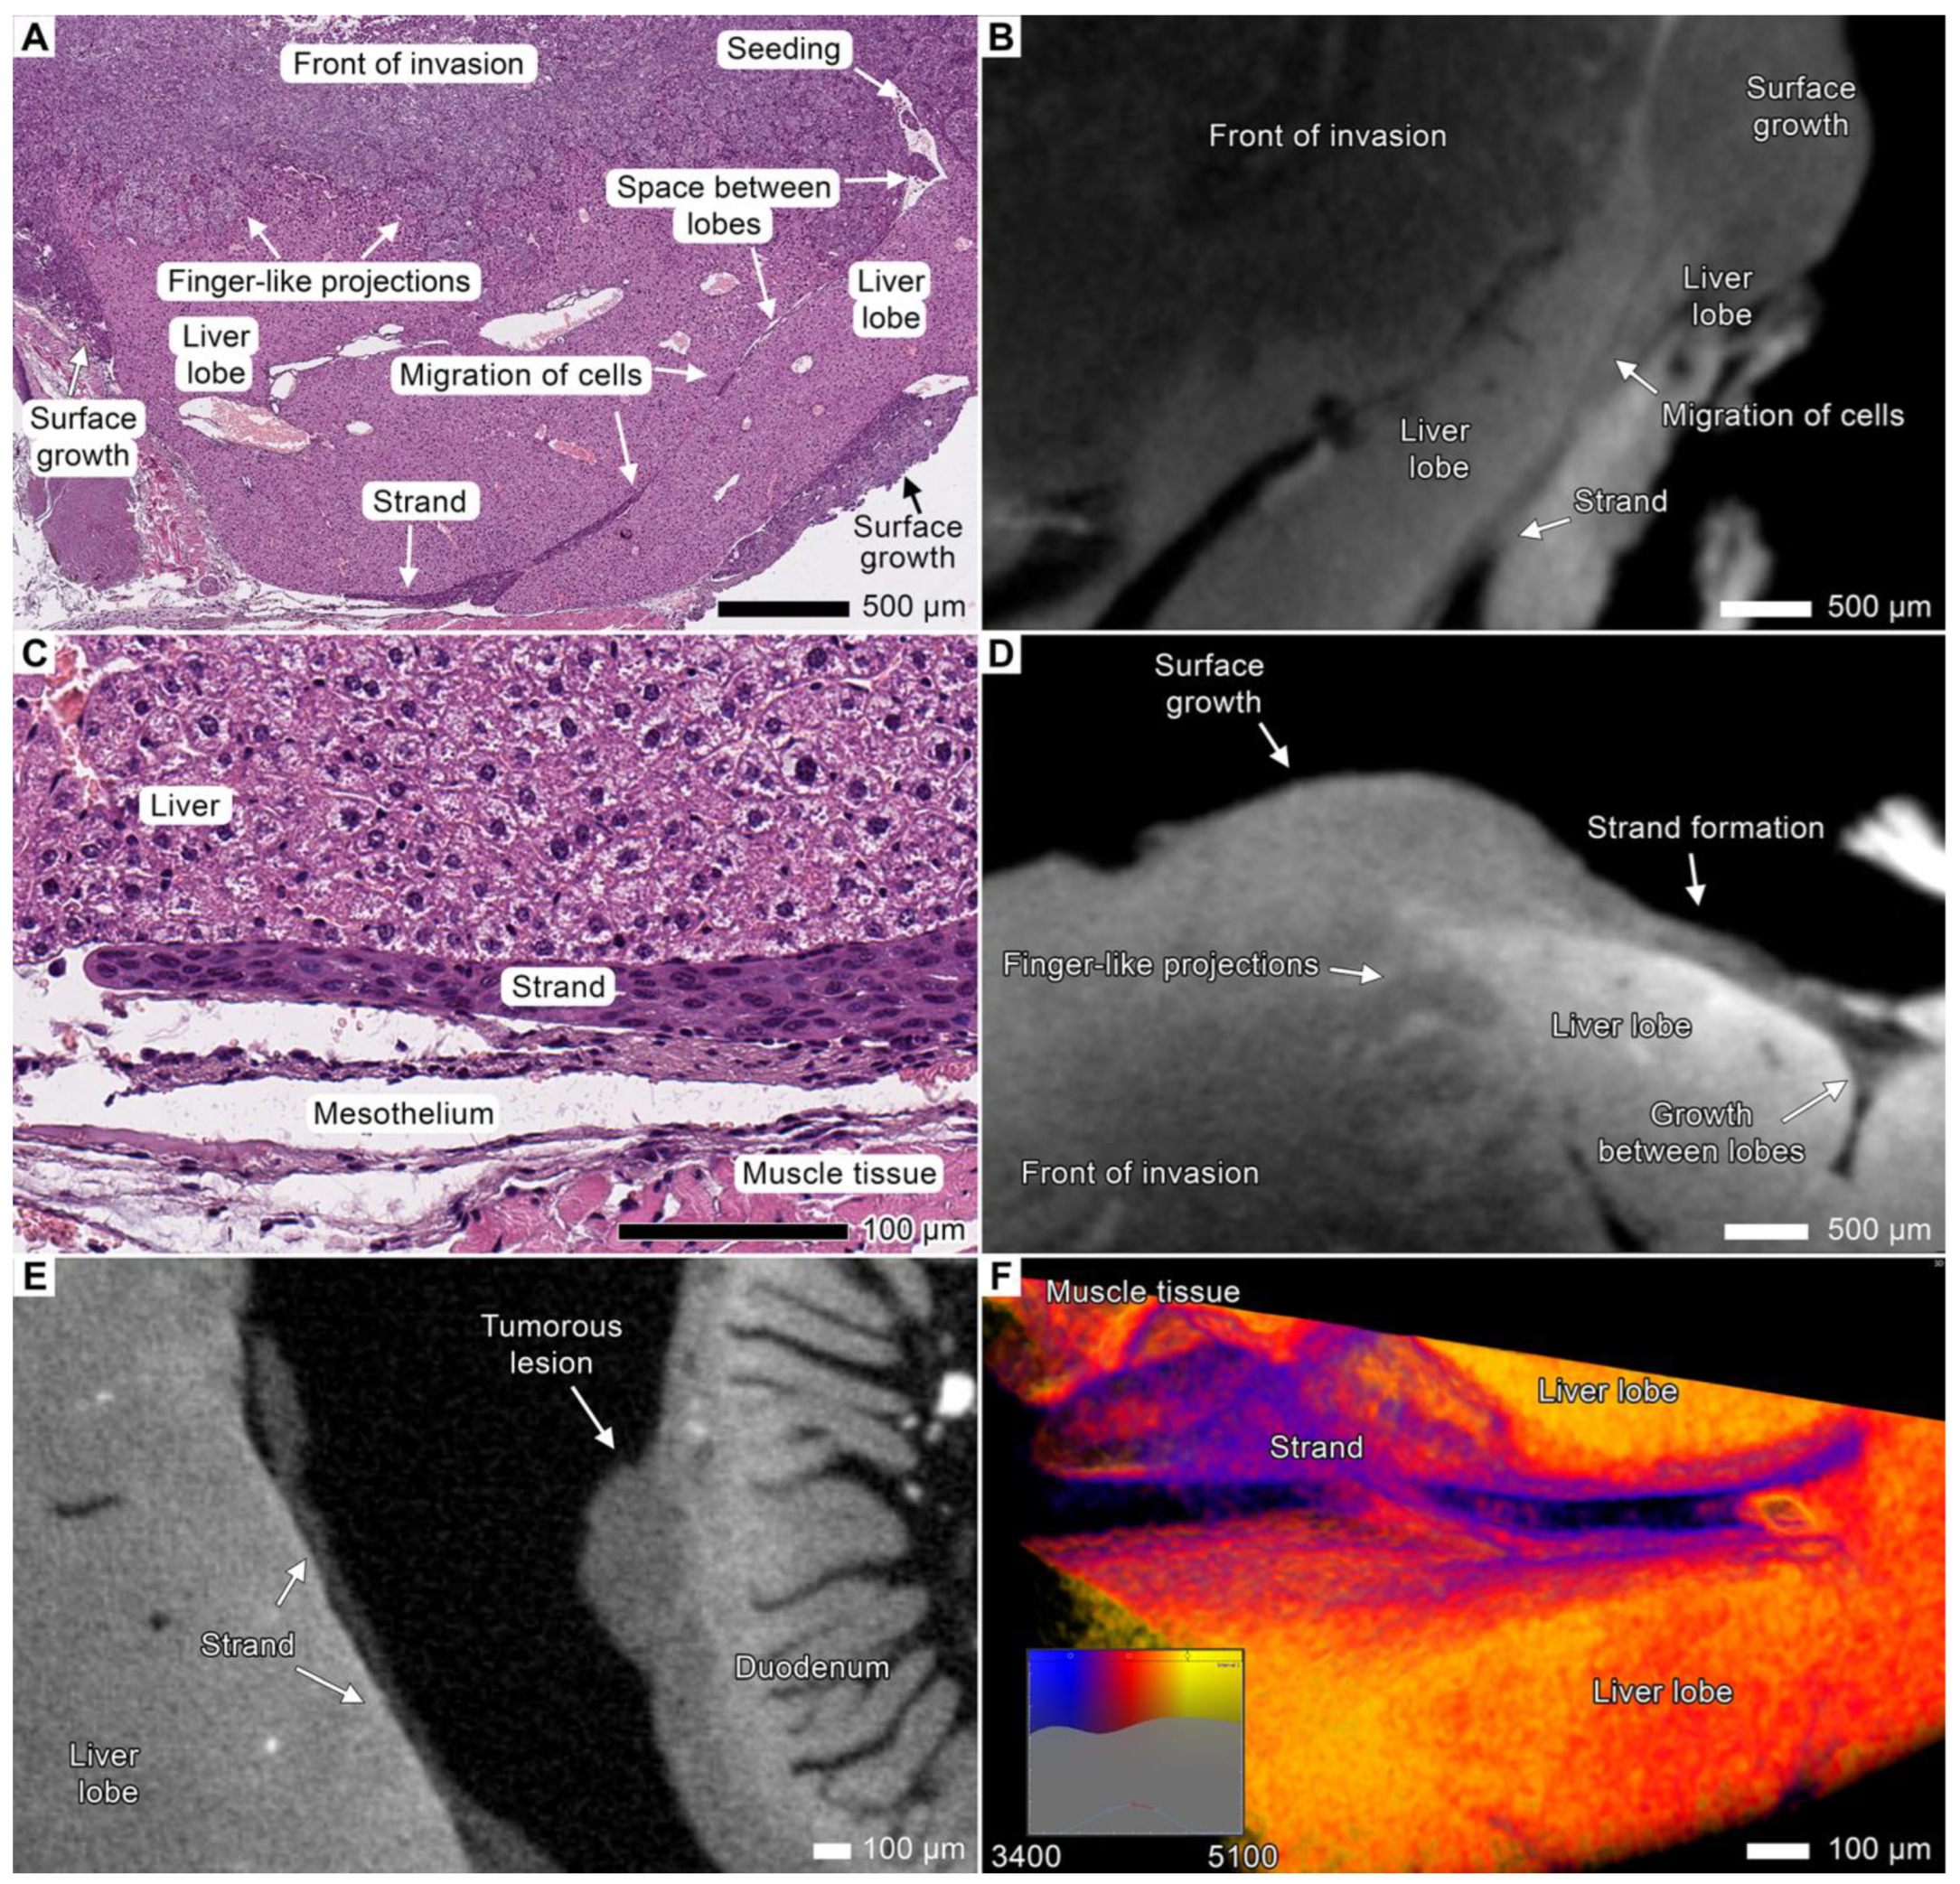

3.7. Stromal Connective Tissues Define Patterns of Invasion

3.8. Expanding the Concept of Tumor Clusters

4.6. The Cyclical Nature of Tumor Dissemination

4.7. The Finger-like Projection Type of Invasion in the Connective Tissue